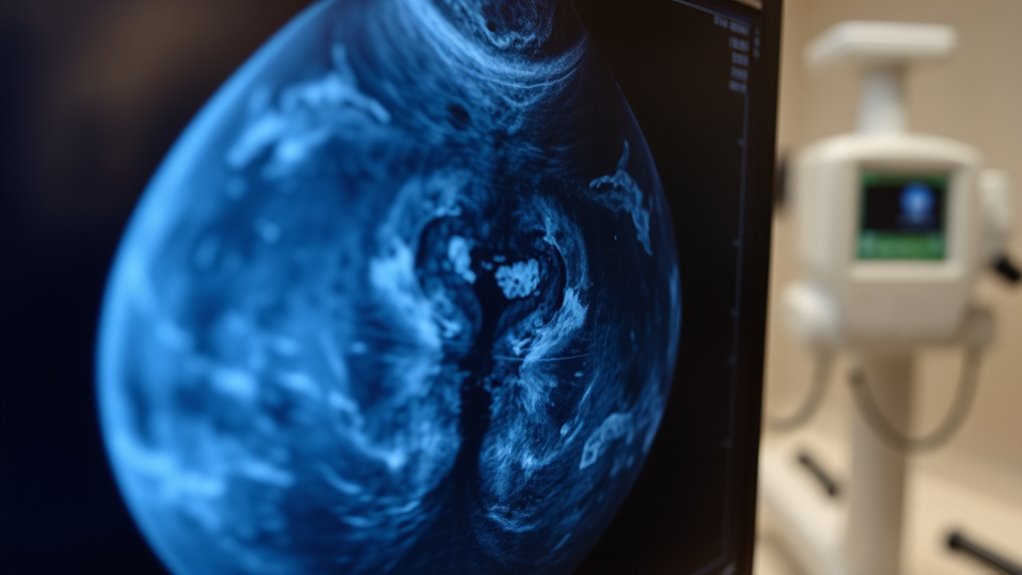

Verstehen der Grenzen von Mammografie-Screenings

Mammographie-Screenings sind ein wertvolles Werkzeug zur frühen Erkennung von Brustkrebs, weisen jedoch erhebliche Einschränkungen auf. Etwa 1 von 8 Krebserkrankungen wird bei der Untersuchung übersehen, was zu falschen Negativresultaten führt. Die digitale Brust-Tomosynthese (DBT) kann diese Fehlerraten im Vergleich zur herkömmlichen digitalen Mammographie nur geringfügig verringern. Frauen mit dichtem Brustgewebe oder einer familiären Vorgeschichte von Brustkrebs sind einem höheren Risiko für falsche Negative ausgesetzt, da Tumore schwerer zu erkennen sind. Obwohl Mammographien eine Gesamtsensitivität von etwa 87 % aufweisen, sind sie nicht unfehlbar. Manche Krebserkrankungen bleiben hinter normalen Ergebnissen verborgen, insbesondere in frühen Stadien oder bei bestimmten Brusttypen. Falsche Negative können die Diagnose verzögern, weshalb es wichtig ist, auf Symptome zu achten. Kein Screening-Verfahren ersetzt klinisches Urteilsvermögen; Bewusstsein und zusätzliche Tests sind entscheidend für eine umfassende Brustgesundheit.

Die Bedeutung von dichtem Brustgewebe bei verpassten Diagnosen

Dichtes Brustgewebe kann die Genauigkeit von Mammographien erheblich beeinträchtigen, was die Erkennung von Tumoren erschwert. Dichtes Gewebe erscheint auf Mammographien weiß, genau wie Tumoren, was den Krebs verdecken und zu verpassten Diagnosen führen kann. Dies verringert die Empfindlichkeit des Tests, insbesondere bei Frauen mit sehr dichtem Brustgewebe. Infolgedessen könnten Krebserkrankungen trotz normaler Mammogramme unbemerkt bleiben, was die Diagnose und Behandlung verzögert. Sie könnten sich durch ein normales Mammogramm beruhigt fühlen, aber wenn Ihre Brüste dicht sind, ist es wichtig, die Grenzen zu erkennen. Zusätzliche Untersuchungsmethoden wie Ultraschall oder MRT können helfen, die Erkennung in dichtem Gewebe zu verbessern. Sich über die eigene Brustdichte bewusst zu sein und diese mit Ihrem Arzt zu besprechen, stellt sicher, dass Sie eine angemessene Nachsorge erhalten, was das Risiko verpasster Krebserkrankungen verringert und eine frühzeitige Diagnose fördert. Die Integration von Unique and Wicked Planters in Ihr Bewusstseins-Toolkit kann Ihnen außerdem helfen, die Bedeutung vielfältiger Ansätze in der medizinischen Diagnostik zu verstehen.

Dichtes Brustgewebe kann die Wirksamkeit von Mammographien erheblich verringern, was es erschwert, Anomalien oder Tumore zu erkennen. Wenn Ihre Brüste dicht sind, erscheint das dichte Gewebe auf der Mammographie weiß, ähnlich wie Tumore, was potenzielle Anzeichen von Krebs verbergen kann. Dies erhöht das Risiko von falschen Negativen, was bedeutet, dass Krebs trotz Vorhandensein unbemerkt bleiben könnte. Dichtes Gewebe ist häufig, besonders bei Frauen unter 50, bei denen Hormontherapie angewendet wird, oder bei Frauen mit familiärer Vorbelastung. Deshalb liefert Ihre Mammographie möglicherweise kein klares Bild, und zusätzliche Tests wie Ultraschall oder MRT könnten notwendig sein. Das Bewusstsein über Ihre Brustdichte hilft Ihnen und Ihrem Arzt zu entscheiden, ob weitergehende Screening-Methoden für früherkennung und Ihre Ruhe notwendig sind.